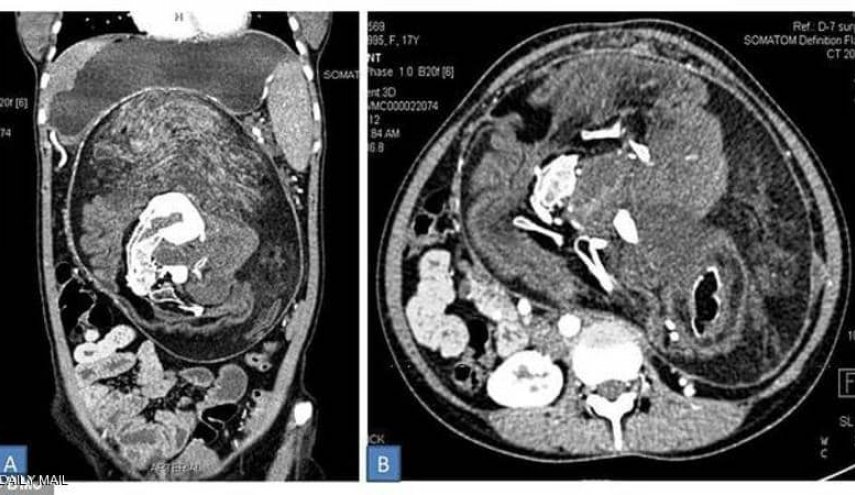

وبعد إجراء تصوير بالأشعة والتصوير المقطعي، اتضحت طبيعة الكتلة الغريبة داخل أحشاء الفتاة وتم التعرف عليها على أنها مجموعة كاملة من الأعضاء والأنسجة، وبدت بعض المناطق مثل الدهون، بينما ظهرت مناطق أخرى مثل الأنسجة الرخوة للأعضاء، ثم بعض الأجزاء الصلبة المكونة من الكالسيوم، والتي بدت بيضاء صارخة في التصوير بواسطة الأشعة المقطعية.

وعند الفحص الدقيق، تبين أن أجزاء الكالسيوم ما هي إلا عظام، وعلى وجه التحديد، فقرات وأضلاع وعظام طويلة.

كان ذلك قبل عامين، عندما قرر الأطباء إجراء عملية جراحية لإزالة هذه الكتلة، التي تبين أنها تحتوي بالفعل على العظام والشعر وعدة أسنان بالإضافة إلى "هياكل تشبه براعم الأطراف".